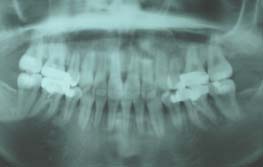

上顎両側4番を抜歯

下顎両側4番も抜歯

上下顎の前突感改善のため第一小臼歯の抜歯を行い最終排列を行いました。